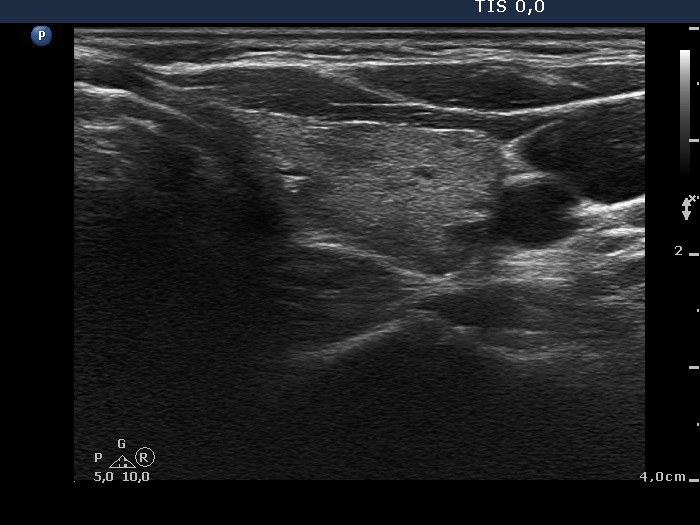

Study on 100 consecutive patients with thyroid nodule - case 006 (ultrasonographic picture 7)

Left lobe, transverse scan. This lobe is echonormal. The presence of small hypoechoic areas raises the possibility of an underlying thyroiditis.